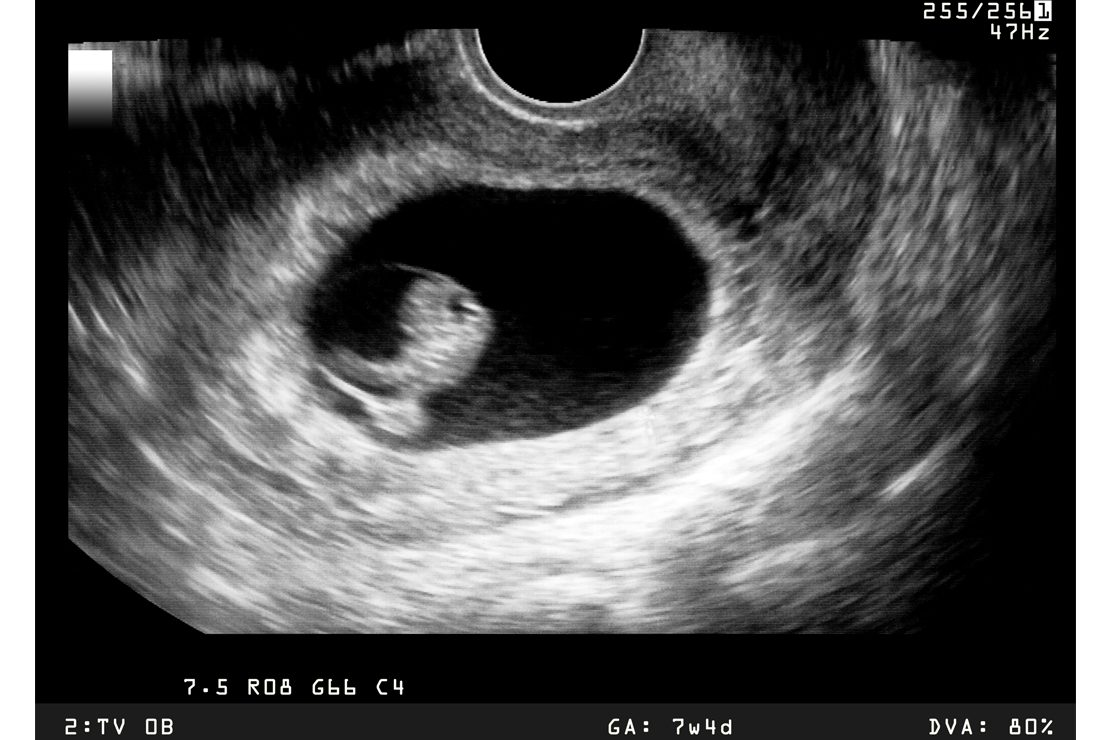

The most common method is nonviable pregnancy ultrasound evaluation.

During an ultrasound, physicians may observe:

• Absence of a developing embryo

• Gestational sac without fetal development

• No heartbeat at expected gestational age

• Abnormal growth patterns